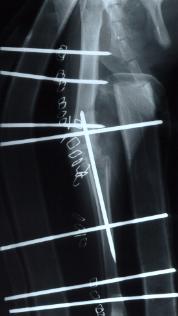

- Verplaatsen van de beenkam op het onderbeen, hierdoor wordt de knieschijf meer naar buiten getrokken waardoor hij gemakkelijker in de sleuf van de femur blijft.

-

- pijltje wijst de verplaatste beenkam aan

- Het uitdiepen van de sleuf in de femur, hierbij wordt met een speciaal freestoestel de sleuf uitgeslepen en gepolierd. De patella komt dieper in de sleuf te liggen en kan niet meer luxeren.